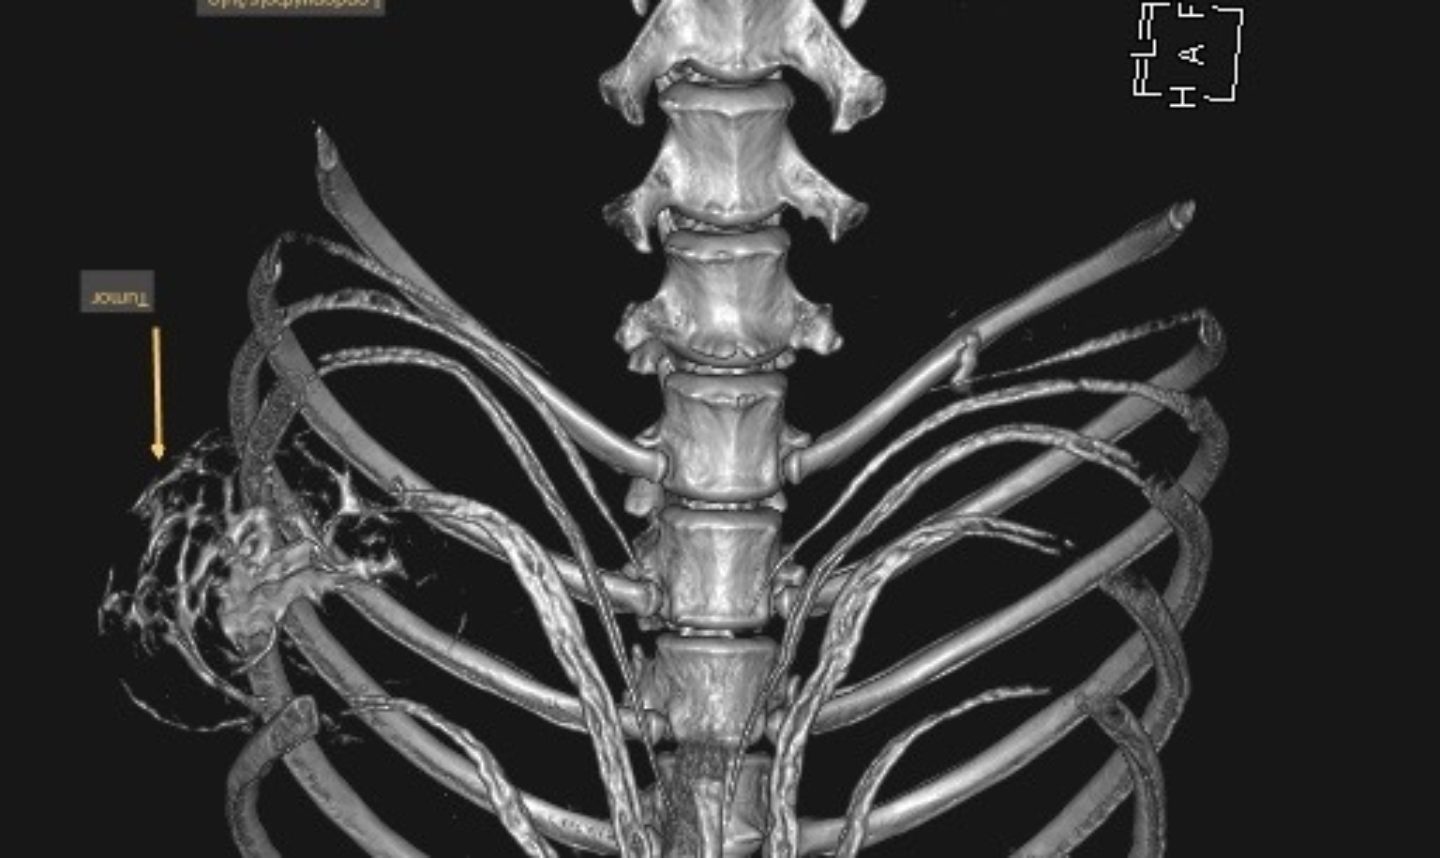

Leo wurde nun nach einer gründlichen allgemeinmedizinischen sowie labortechnischen Untersuchung zur Computertomographie (CT) angemeldet, die in Vollnarkose stattfinden muss. Mit dieser Technik werden mit Hilfe von Röntgenstrahlen ein Millimeter dünne Schichtaufnahmen angefertigt und damit das genaue Ausmaß des Tumors dargestellt. Zum anderen kann im Vergleich zu einem konventionellen Röntgenbild eine überlagerungsfreie Aussage über den Zustand des benachbarten Weichteilgewebes getroffen werden. Diese Informationen sind für den Chirurgen unumgänglich, damit er die Operation planen kann.

In diesem Fall wurde durch die CT das enorme Ausmaß der Umfangsvermehrung deutlich, sodass insgesamt drei Rippen inklusive der dazwischenliegenden Muskeln in Mitleidenschaft gezogen wurden. Die gute Nachricht war, dass der innerhalb der Bauchhöhle unmittelbar anliegende linke Leberlappen, Magen und Milz sowie der hintere Anteil des linken Lungenflügels im Brustkorb noch nicht vom Tumorwachstum erfasst waren.